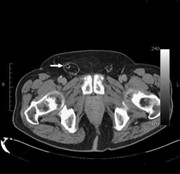

A rare case of appendicitis incarcerated in an inguinal hernia

Eduardo Smith-Singares and others

Journal of Surgical Case Reports, Volume 2016, Issue 6, June 2016, rjw096, https://doi.org/10.1093/jscr/rjw096